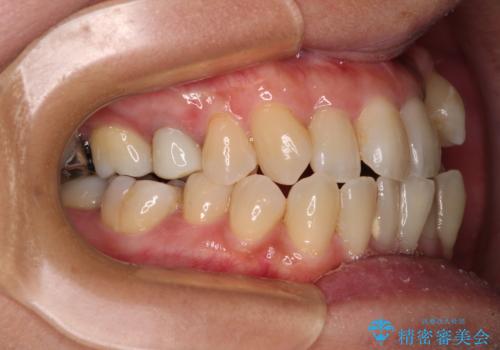

受け口と八重歯を改善 インビザライン矯正治療

- 前歯のデコボコや八重歯を治したいとのことで来院された患者様です。

受け口傾向の骨格であり、前歯はクロスバイトまたは切端咬合となっており、下顎を中心に歯列全体の後方移動を行い、IPR(歯と歯の間を削る)によってデコボコが解消するように設計し、インビザラインにより治療を行うこととしました。

受け口傾向のインビザライン矯正は比較的治療を行いやすいため、きれいに仕上げることができました。舌の突出癖が顕著であったため、改善のためのトレーニングをしっかりと行っていただきました。